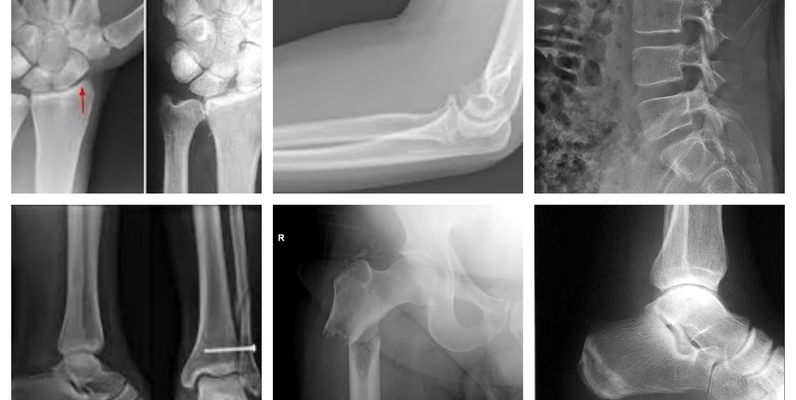

多区域骨折 X 射线数据集 10580 张 含训练测试验证集 骨折 / 非骨折医学影像数据(下肢 / 上肢 / 腰椎 / 臀部 / 膝盖等全解剖区域)

本次分享多区域骨折 X 射线专业数据集,总计 10580 张高质量放射图像,包含骨折与非骨折两类标注数据,全面覆盖人体所有解剖身体区域 —— 下肢、上肢、腰椎、臀部、膝盖等关键部位均有完整影像收录,数据维度丰富且贴合临床实际场景。

数据集已按 AI 模型开发标准,分为训练文件夹、测试文件夹、验证文件夹三大模块,每个模块均同步包含骨折与非骨折两类 X 射线图像,无需额外整理即可直接用于算法训练与模型验证,降低数据预处理成本。

全解剖区域覆盖 + 骨折 / 非骨折双类别标注 + 训练 / 测试 / 验证三分组 + 10580 张足量数据,满足医学 AI、学术研究、教学实践等多场景使用需求,数据合规可用,直接下载即可投入应用。